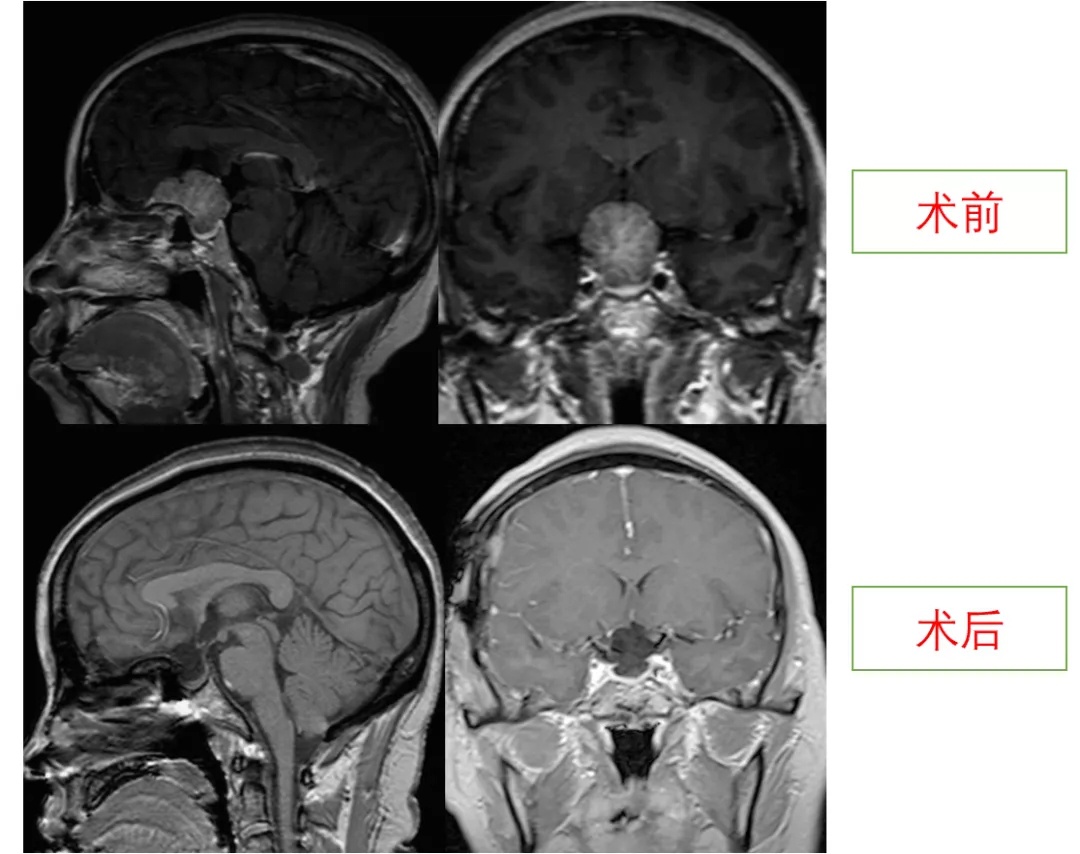

2018年,49岁的李女士发现自己双眼视物不清,数次到当地医院眼科检查,却未发现明显异常,考虑为“老花眼”。随后,她视力模糊逐渐加重,左眼比右眼进展更快。近日,李女士来到温州医科大学附属第一医院就诊,通过头颅CT和磁共振检查发现其颅内肿瘤,明确为“鞍结节脑膜瘤”。原来导致李女士视力下降的“元凶”,就是隐藏在两侧视神经之间的肿瘤。

在经过手术后,患者双眼视力好转,右眼的恢复更加明显。这也与术前左眼视力更差,术中看到肿瘤与左侧视神经粘连较紧密相关。复查头颅磁共振,显示肿瘤已完全切除。